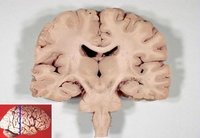

前腦葉白質切除術當實行這一手術時,醫生需要在病人的顱骨兩側各鑽一個小孔,然後將腦白質切斷器從洞中伸入病患腦部,在每側選擇三個位置實施手術。這個儀器的外形就像是一把修長而精緻的螺絲刀,不過它的頭部側面開了口而且沒有尖端。然後醫生需要拉動手柄,開口處的鋼絲在拉動作用下便會凸起,切斷神經纖維。

現在對前腦葉白質切除術所做出的評價一般都是負面的,這主要是因為在當時的簡陋條件下,對大腦所實施的手術精度很低,對術後效果的評價也沒有客觀、可信的標準。而且手術對象在經過手術後往往喪失精神衝動,表現出類似痴呆、弱智的跡象。